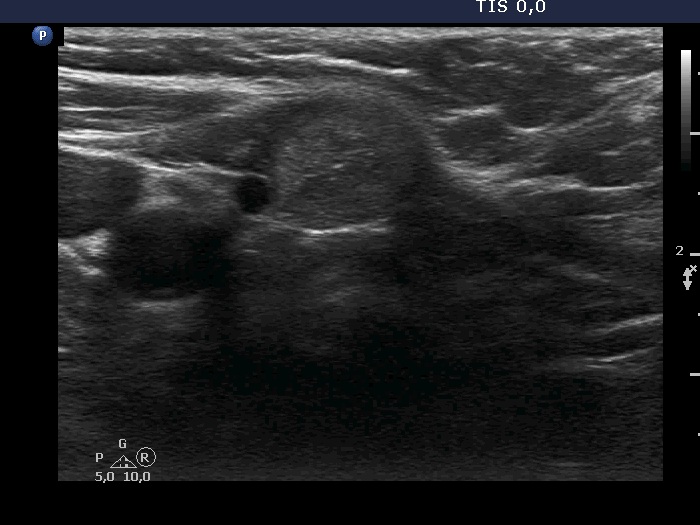

Ultrasonography. The thyroid was echonormal. There was a moderately hypoechoic nodule in the isthmus. The nodule had several intranodular hyperechogenic figures, probably back wall figures. The nodule did not show increase in size over the part two decades.